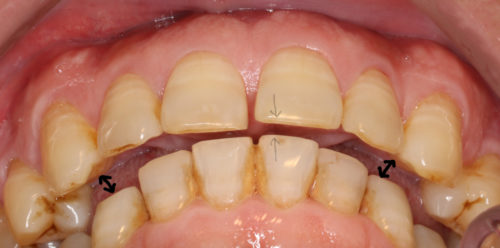

前歯が当たっていないと、問題があるのは、麺類が食べにくいことだけではありません

前歯が当たることで、奥歯を守る、というとても大切な機能が疎かになってしまうのです

つまり、奥歯にダメージが蓄積し、いずれは抜歯に至る可能性が高いということです